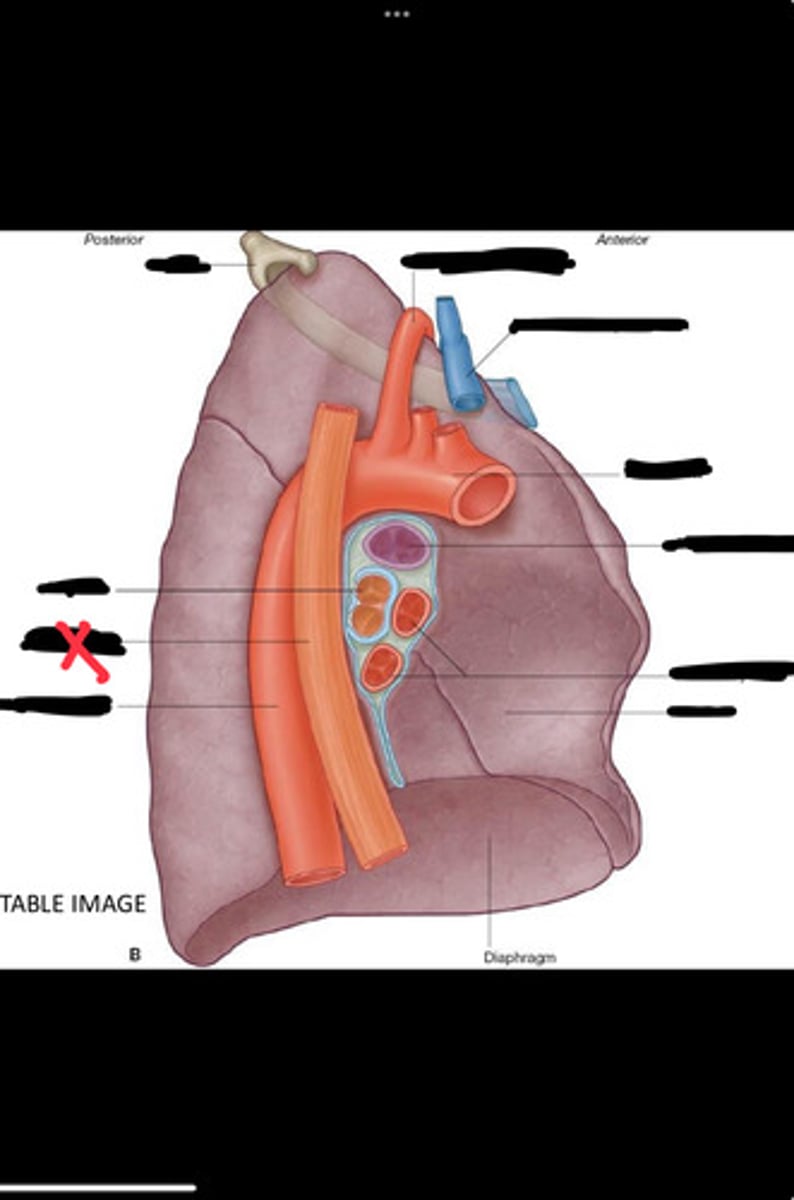

Diaphragm

Inferior vena cava

Superior vena cava

Subclavian vein

Right bracheocephalic vein

Subclavian artery

Esophagus

Bronchus

Rib 1

Left subclavian artery

Left brachiocephalic vein

Aortic arch

Pulmonary artery

Pulmonary vein

Heart

Left brachiocephalic vein

Azygos vein

Esophagus

Bronchus

Fibrous pericardium

Parietal layer of serous pericardium

Pericardial cavity

Visceral layer of serous pericardium

Junction between fibrous pericardium and adventitia

Heart

Thoracic aorta

Rib 1

Pulmonary artery

Bronchus to superior lobe